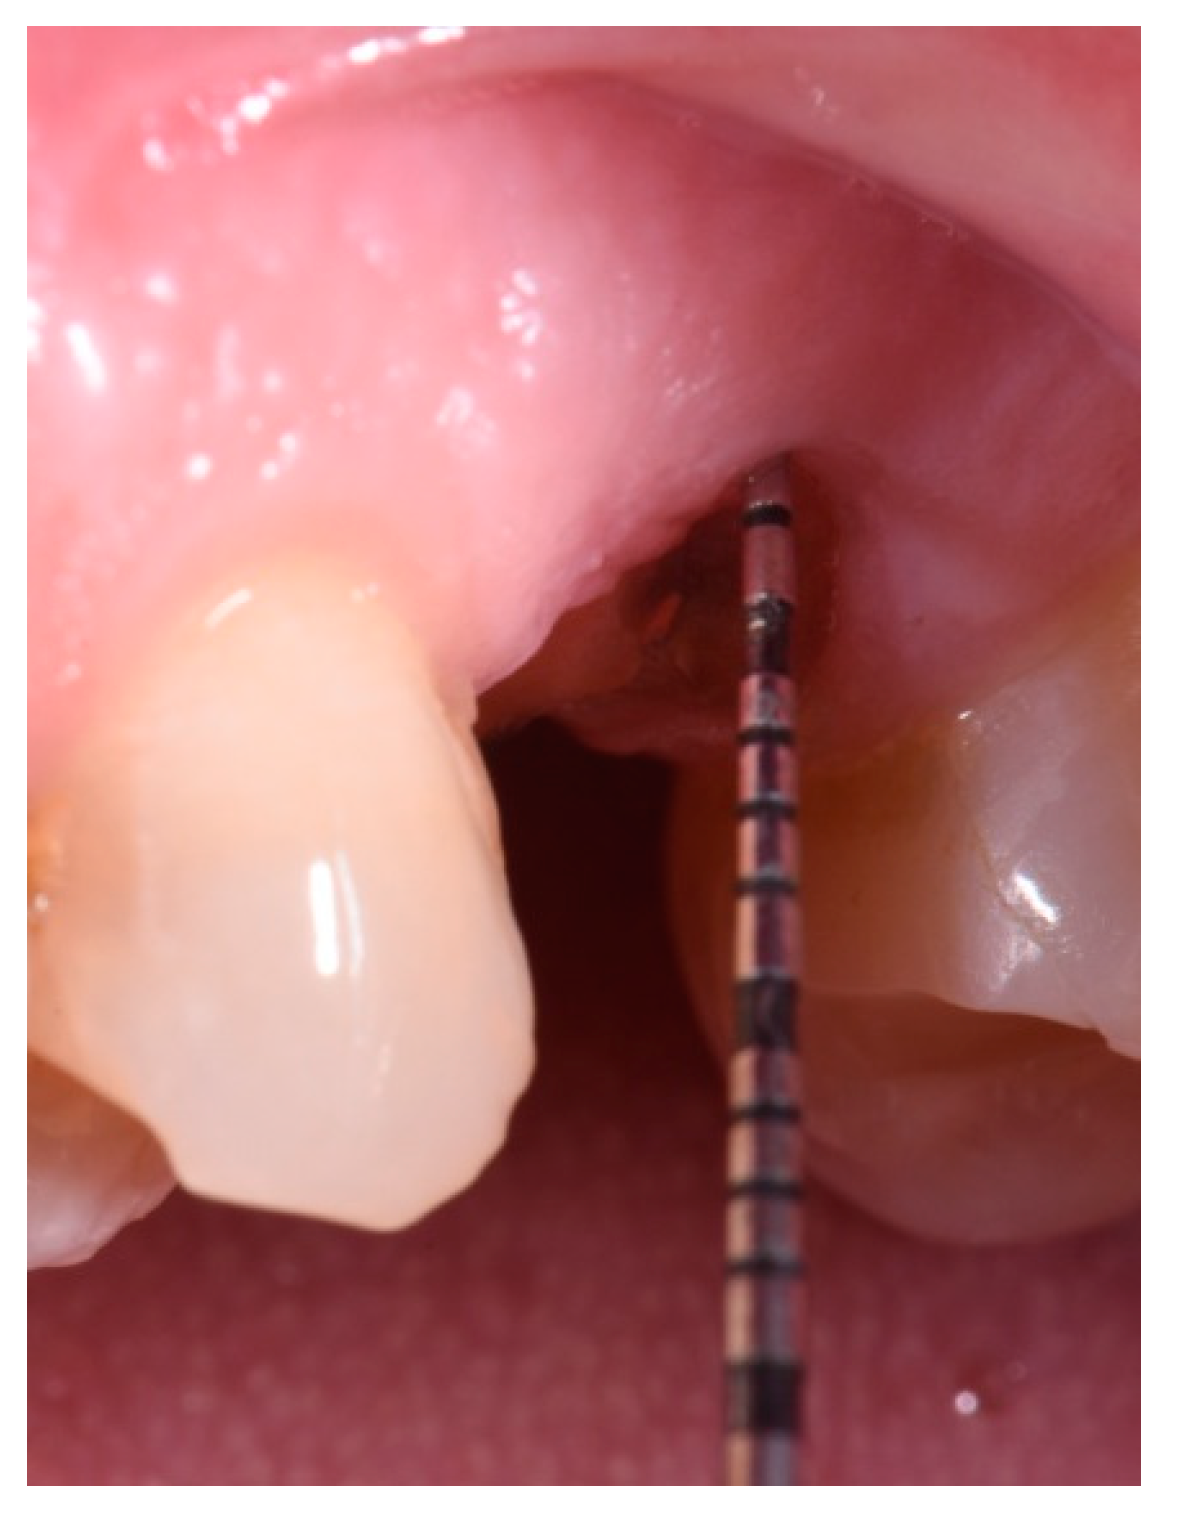

- Measurement in mm of the depth of insertion of the instrument into the gingival sulcus;

- Positioning of the insert;

- Approximation of instrument entry angle with respect to the root;